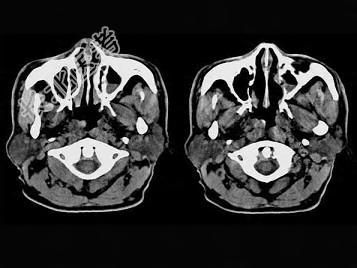

- 单项选择题男,61岁, 流鼻血三天。如图所示最可能的诊断为 ( )

A、鼻咽淋巴滤泡增生

B、鼻咽腺样体增生

C、鼻咽纤维血管瘤

D、小唾液腺瘤

E、鼻咽部息肉